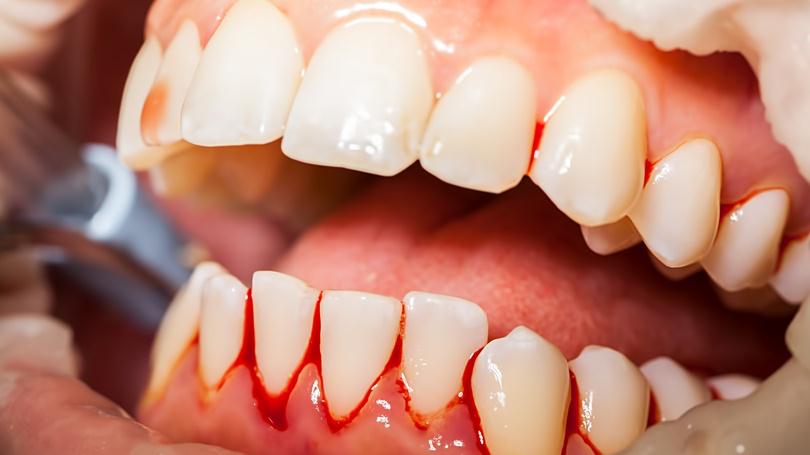

Brushing your teeth is crucial to maintain good dental health. Brushing removes the bacteria that promote tooth decay and some plaque that can cause gum disease. You brush your teeth on a daily basis. But do you think you know the proper technique to do it? Here’s a simple brushing technique to keep your pearly whites healthy:

The Modified Bass Brushing Technique is the most widely accepted and most effective method of brushing for adults. Following steps will help you practice the modified bass technique with much ease:

In case of deep stains and calculus visit your nearest dentist for professional cleaning.We at dental dental lifeline use high ultrasonic scaler for the quality same.